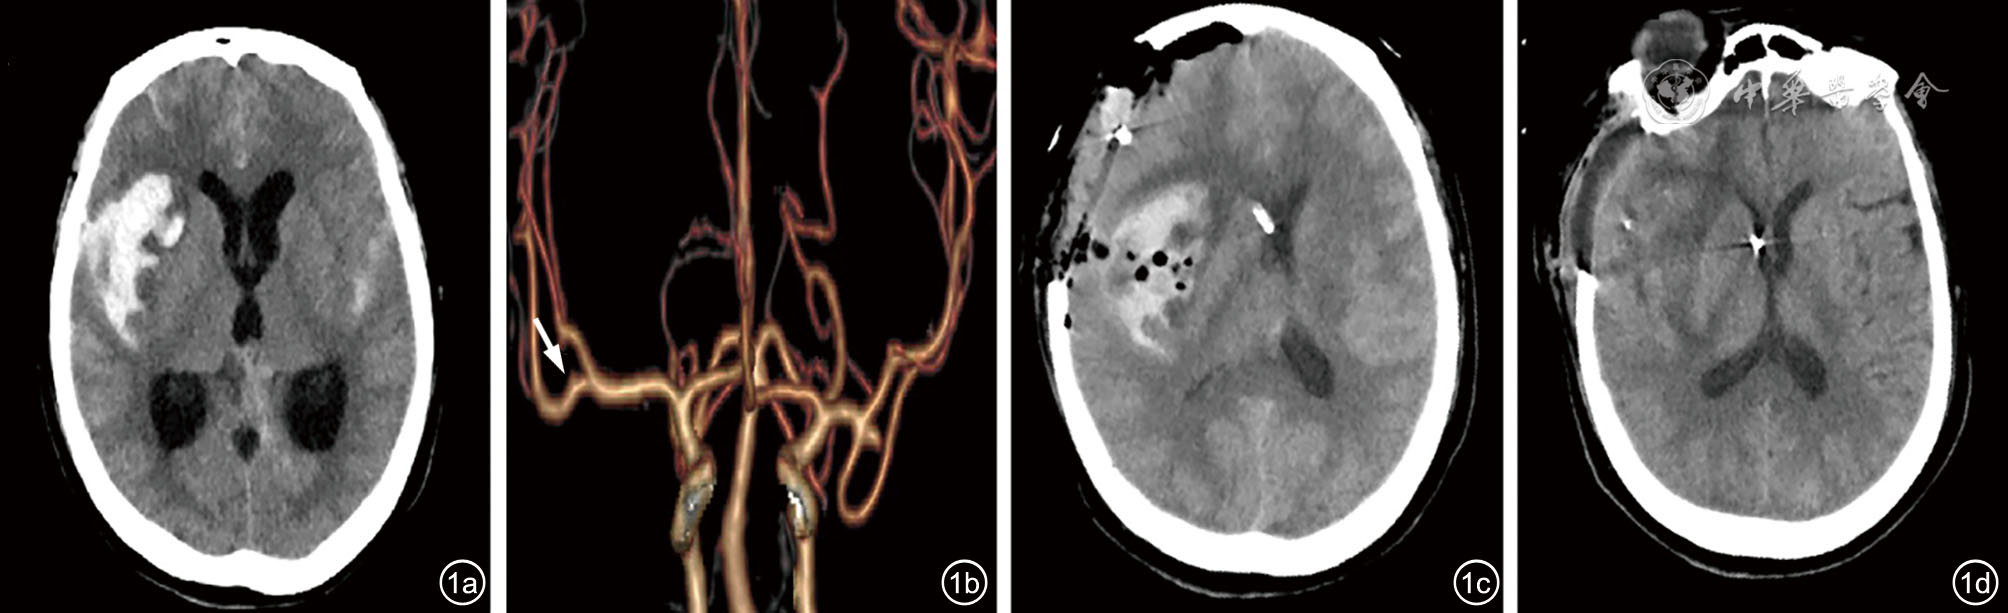

图1 病例1影像资料。图a:入院CT显示较厚的SAH,伴右外侧裂-岛叶血肿,脑室扩大、少许积血;图b:CTA显示右侧大脑中动脉分叉后下干可疑动脉瘤(箭头),术中证实为责任动脉瘤,同时可见左侧大脑中动脉分叉动脉瘤;图c:术后当天CT显示右额岛叶积血,中线左偏;图d:术后第14天CT显示位于右额岛叶、脑室及脑池的出血较前部分吸收。此时,患者的PSH症状已不再发作 注:SAH 为蛛网膜下腔出血;CTA 为CT 血管造影;PSH 为阵发性交感神经过度兴奋